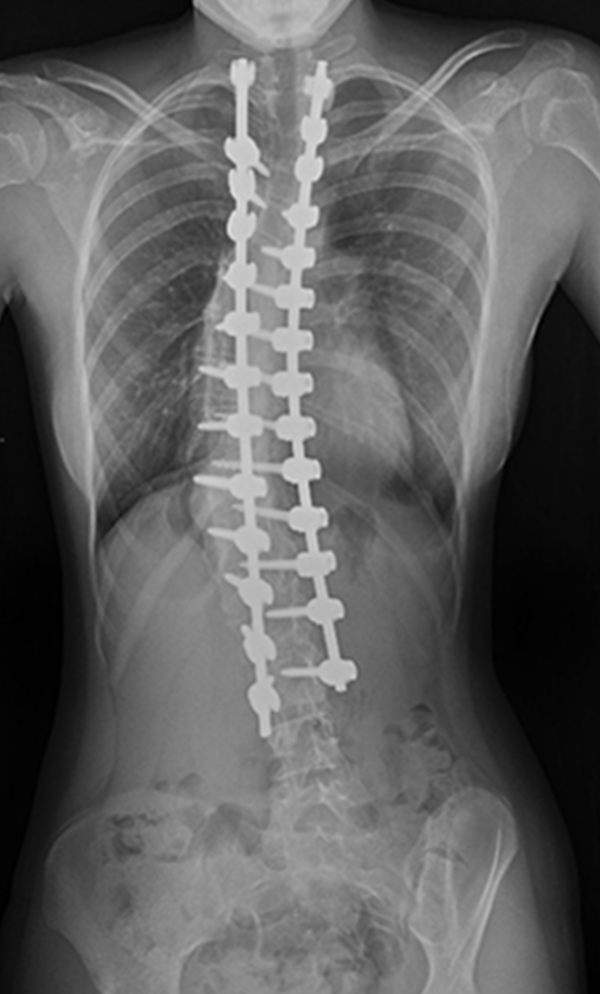

Gallery : Before - After